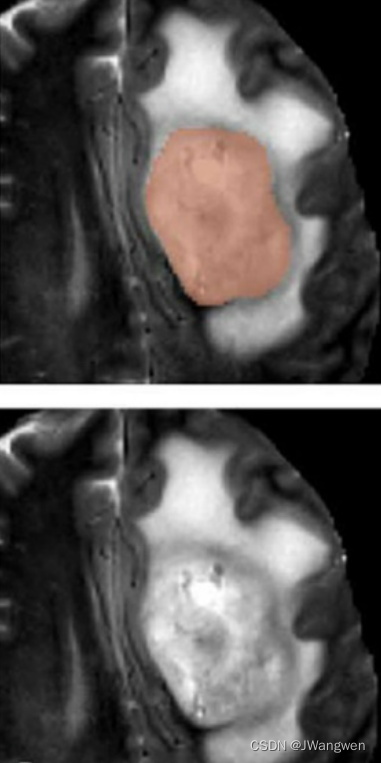

下图所示, 蓝色区域是增强瘤(enhancing tumor),它环绕的里面绿色那些是坏疽(ju)(necrotic components),坏疽就是细胞坏死然后液化.所以这些坏疽还被被称为非增强瘤(non-enhancing tumor).